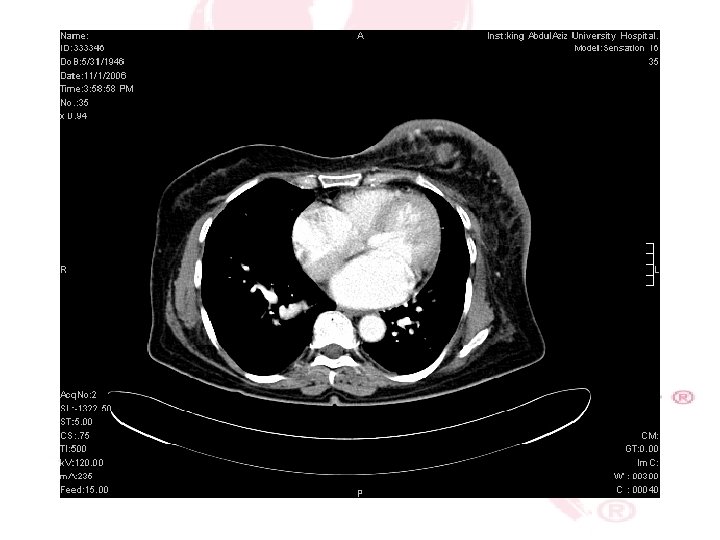

CT SCAN CHEST , ABDOMEN &PELVIS